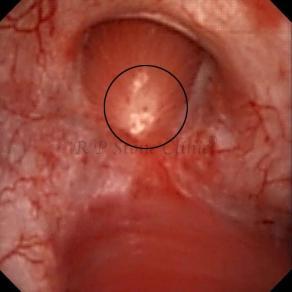

These images are taken as snap shots from the video recording of RIRS Surgery done at our hospital. These are Randall’s Plaques seen with Digital FLEX XC & Digital FLEX XC S. The cream or whitish patches are seen on the tips of RENAL PAPILLAE as seen in images below.

Kidney stone is a solid mass of CRYSTALS. It is the process of crystallization which initiates the formation of kidney stones. This happens in nephrons or units of kidney. Once a small crystal is formed, it can both grow & unite with other crystals leading to the formation of small concretion which eventually forms a stone. Once these large crystals detach from the collecting ducts, the process of stone formation starts in the renal collecting system. A recurrent kidney stone former is advised to know a little bit about something known as Randall’s plaque. Alexander Randall discovered plaques on the renal papillae eight decades back based on examination of 1154 pairs of autopsied Kidneys. He described these renal papillary lesions as cream colored or milk patch areas composed of calcium phosphate & calcium carbonate. These plaques could act as NIDUS for formation of KIDNEY STONE. Calcium Oxalate stone can form on this nidus & then detaches from this plaque to become a free floating stone in the collecting system of kidney